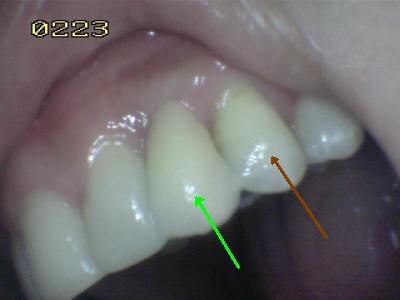

Prueba  de la porcelana  El matiz del póntico (flecha verde) se determino con el primer premolar (flecha marrón); en palatino se observa el contacto dentario antagonista en oclusión habitual. Note como el brazo palatino del retenedor envuelve casi toda la cara palatina; el ideal  es que sea mayor a 180º ; para lograr una máxima retención y estabilidad

Vista vestibular. El matiz del póntico (flecha verde) se determino con el primer premolar (flecha marrón) Antes del tratamiento